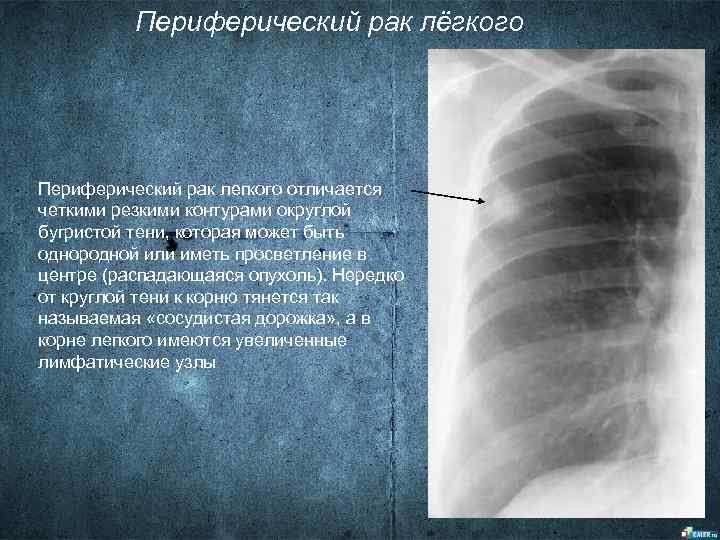

Иллюстрации по теме очагового и инфильтративного туберкулеза